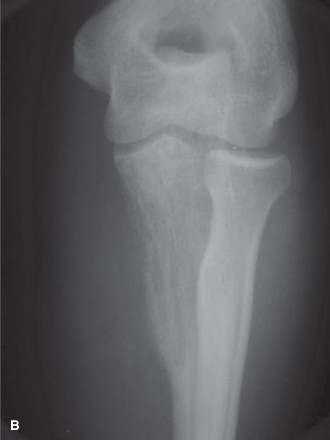

This image potentially depicts a radiographic representation of a Ewing sarcoma in a long bone, highlighting the typical diaphyseal involvement and periosteal reaction.

Long Bones

- Diaphyseal Involvement: ES frequently involves the diaphysis or metadiaphysis, often leading to significant cortical destruction and soft tissue extension. The peritumoral edema and reactive zone are extensive, requiring wide margins that may necessitate resection of a substantial segment of the bone.